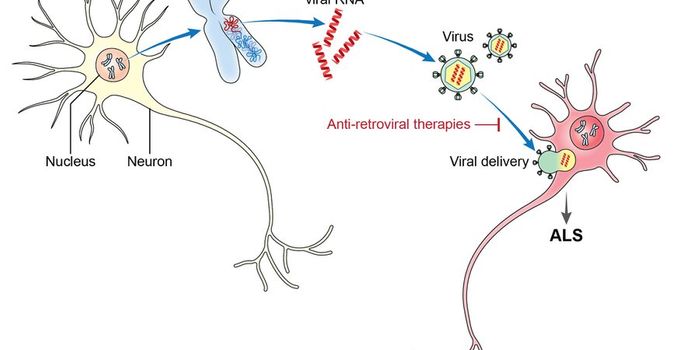

JAN 06, 2016NeuroscienceThe neurodegenerative disease known as ALS (amyotrophic lateral sclerosis) has no cure and no known cause. Sometimes ref ...

OCT 05, 2015NeuroscienceMost people don’t realize that the genetic remnants of viruses from millions of years ago still reside in human DN ...